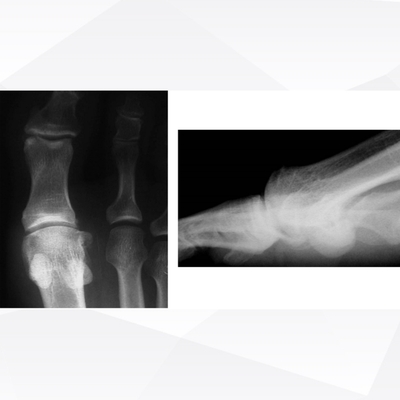

Click on an image below to view more info.